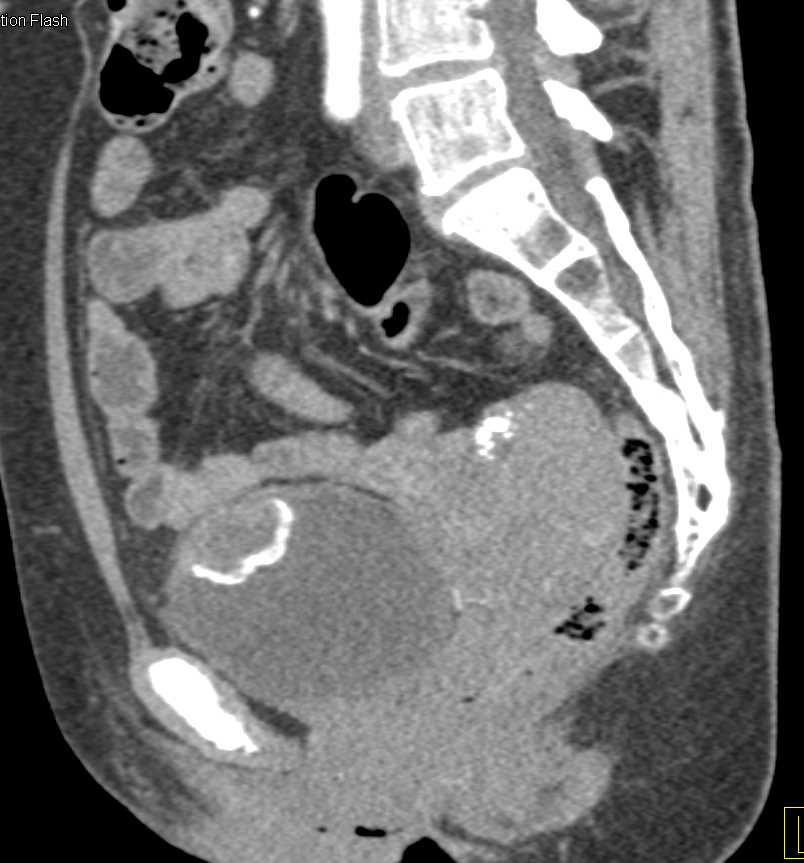

Urachal Carcinoma of the Bladder